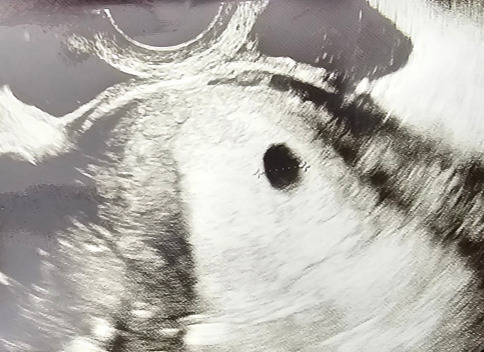

그렇게 혼자 일주일 동안 걱정하며 끙끙 앓다 산부인과에 가서 질 초음파 검사를 받은 후 아기집을 확인했다. "임신입니다."라는 의사의 말에도 나는 의사가 오진일 것이라 생각하고 나도 모르게 임신을 강하게 부정하고 있었다. 산부인과 진료를 마치고 집으로 가는 길에 펑펑 울었다. 그러곤 이제는 신랑에게 말을 해야 할 것 같아 우울한 기분에 카톡을 보냈다. 마음이 복잡하고 두려웠지만, 그렇다고 해서 아이를 지우는 잘못된 선택은 생각하지 않았다. 그저 나에게 현실을 받아들일 시간이 필요했다.